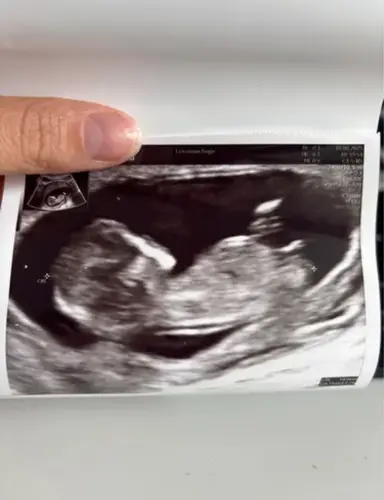

Iemand die hier iets in ziet? Deze echo is van precies 12 weken! 2 maart uitgerekend 🩵🩷

Iemand die hier iets in ziet? Deze echo is van precies 12 weken! 2 maart ui ...

Ik zie 2 streepjes , meisje 🩷

Hij of zij ligt zo in een kommetje. Ik vind het lastig om te zien. Is iemand hier misschien heel goed in hihi.